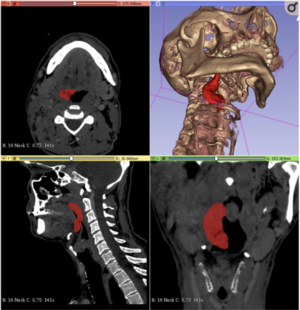

- 1.24 Individual Dose Planning in Radiosynoviorthesis Treatment: Step by Step

- 1.25 A Patient-Specific Numerical Model of the Ankle Joint for the Analysis of Contact Pressure Distribution